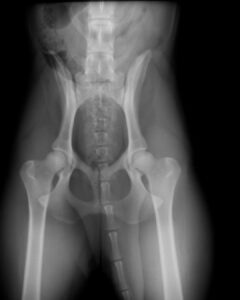

I studien på över 114 000 svenska unga hundar har forskare vid SLU och SKK kartlagt hur utbrett det faktiskt är med höft- och armbågsdysplasi. Om du har en reaktiv hund är det här något du absolut behöver ha koll på, så läs vidare för att lära dig mer!

Har tittat på röntgenresultat från en enorm mängd hundar och sett att förekomsten av höftledsdysplasi (HD) och armbågsdysplasi (ED) varierar kraftigt. I vissa raser är det tyvärr mer regel än undantag att hunden har förändringar i sina leder – och det här uppdagas ofta redan vid den allra första röntgenkontrollen som unga hundar får.

Här är några av de mest uppseendeväckande siffrorna från studien:

- Dogue de Bordeaux: 75 % har HD och 40 % har ED.

- Chow Chow: 65 % har ED.

- American Staffordshire Terrier: Över 64 % har HD och nästan 35 % har ED.

Men siffrorna är höga även hos våra vanligaste familjehundar som golden retriever, labrador och schäfer. Det som är mest kritiskt för oss med reaktiva hundar är att studien bekräftar att hundar med sämre höfter också ofta har sämre armbågar. Det betyder att hunden kan bära på en dubbel belastning som vi inte alltid ser med blotta ögat.

- Röntgen är guld värt: Även om din hund är ung och ser pigg ut – ger en röntgen dig svar som är svåra att få på annat sätt. Om din fysioterapeut eller veterinär misstänker att hunden har ont är detta ett naturligt och viktigt steg att ta.